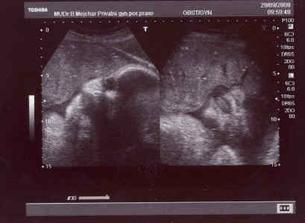

4.6. - opět kontrola a další UTZ (další screaning) - Zdenda byl tentokrát v ordinaci s námi!!! pan doktor nám natočil i DVD....miminko se na UTZ krásně vrtělo a pak nám pan doktor prozradil, že to bude asi holčička 🙂)...

V dalším týdnu - (od 9.6.) - 22.tt. už vnímám pohyby pravidelněji a jistěji...Asi v úterý, když jsme se s mimčem uvelebili v posteli na zádech, krásně jsem ucítila ťukání do bříška....hned jsem zavolala i Zdendu a také mi hned hladil bříško, ale mimčo ještě tolik necítil...2.7. jsme šli na další kontrolu, princezna krásně vyrostla - už má 1kg a pan doktor se smál, že se předbíhá o 14 dní. Pohyby začínají být intenzivnější - holčička krásně kope a je už to hezky cítit navenek. Zdendu jsem kvůli tomu v noci vzbudila, aby se mohl pokochat a naše fotbalistka už pokopala i Martinku a Terezku 🙂).